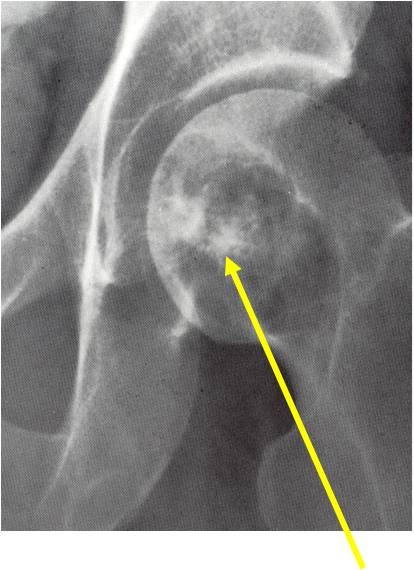

- Epiphyses of long bones

- Most commonly proximal femur, proximal humerus, distal femur, proximal tibia

- Usually osteolytic, expansile lesion

- May be focally calcified

- Often a sharp interface between tumor and surrounding bone

- Overlying cortex is usually thin, but intact